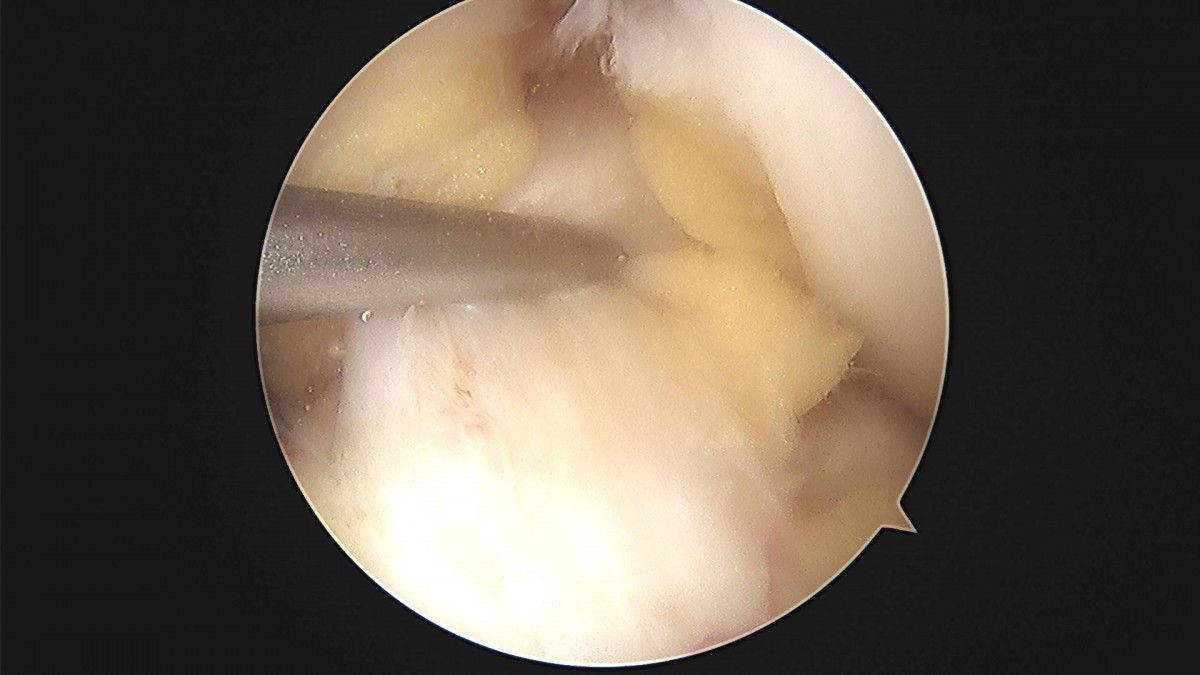

배우한 원장님 무릎 반월상 연골판 절제술 한복O 환자

8b0c7da4bf0a0c139df98fc62b3e688e_1702368995_6016.jpg